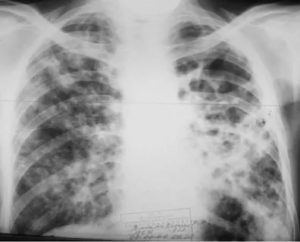

Пятна на легких размером более 1 мм и менее 1 см считаются очагами.

На рентгеновском снимке можно увидеть от 1 до нескольких очагов, расположенных на значительном расстоянии друг от друга или группой.

Если площадь распределения очагов не превышает по площади 2 межреберных пространства, поражение (диссеминация) считается ограниченным, а при распределении очагов на большей площади – диффузным.

Основными критериями оценки очаговых затемнений считаются:

- площадь распространения и расположение очагов;

- контуры затемнений;

- интенсивность затемнений.

При расположении одного или нескольких затемнений в верхних отделах легкого – однозначный признак туберкулеза.

Множество очагов при ограниченном распространении является признаком очаговой пневмонии или результатом распада туберкулезной каверны, расположенной, как правило, несколько выше обнаруженных очагов.

В последнем случае, на снимке может наблюдаться еще и круглая или кольцевидная тень.

В качестве причины появления одиночного затемнения в любой части легкого, в первую очередь, рассматривают вероятность развития рака или метастаза опухоли. Об этом же свидетельствуют четкие контуры тени. Нечеткие контуры свидетельствуют о воспалительном происхождении затемнений.

Для оценки интенсивности затемнений, их сравнивают с изображением сосудов, визуализирующихся на снимке.

Если выраженность очага уступает тени сосуда – это малоинтенсивное затемнение, характерное для очаговой пневмонии или инфильтрированного туберкулеза.

При среднем и сильном затемнении очага, когда выраженность равна или темнее сосудистого рисунка, можно судить о затухании туберкулезного процесса.

Поскольку обширная диссеминация очагов может свидетельствовать о более 100 заболеваниях, для разграничения причин, следует оценивать размеры затемнений. Так, мельчайшие очаги, покрывающие всю площадь легкого, могут означать пневмокониоз, милиарный туберкулез или очаговую пневмонию.

На снимке мелкоочаговые затемнения